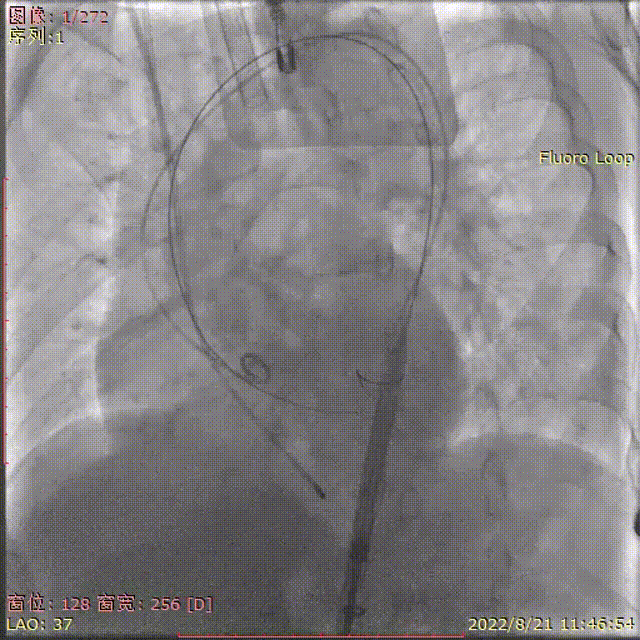

术中剪影

手术影像记录

输送器顺利过弓跨瓣

瓣膜初始定位

工作位多角度评估瓣膜形态,位置理想

缓慢稳定完全释放瓣膜

球囊后扩,改善瓣膜形态

最终造影,位置理想,无瓣周漏